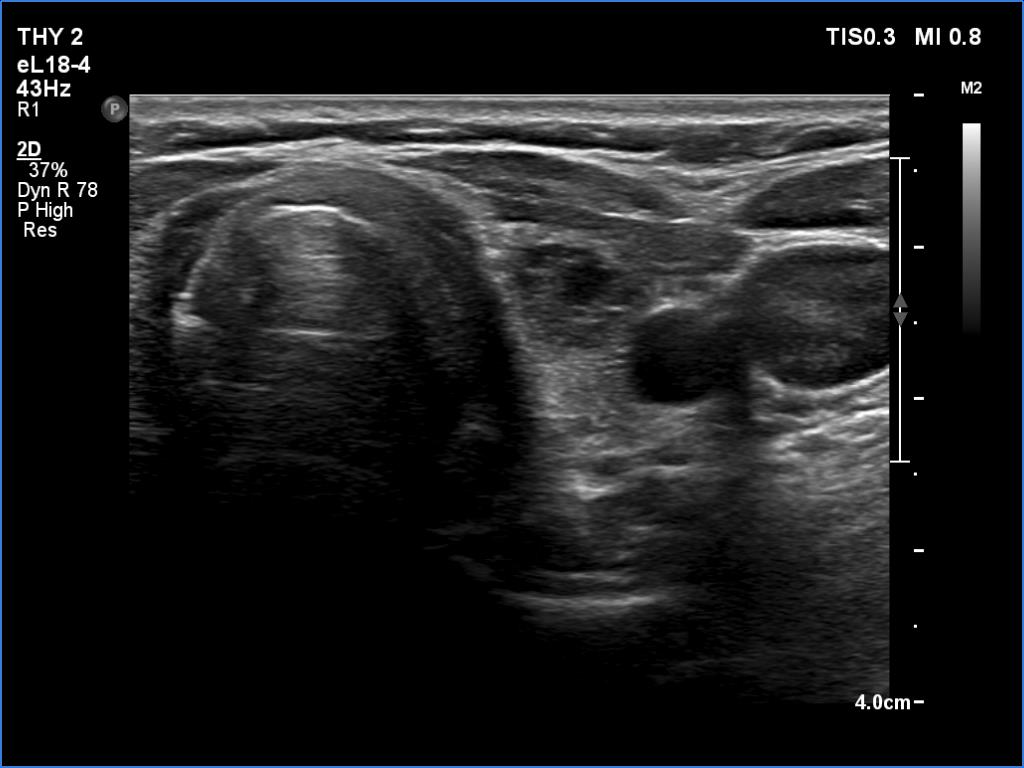

Subacute granulomatous thyroiditis - case 1514

Examination a year after the first visit (ultrasonographic picture 5)

Left lobe, transverse scan. The size of the discrete lesion did not change.